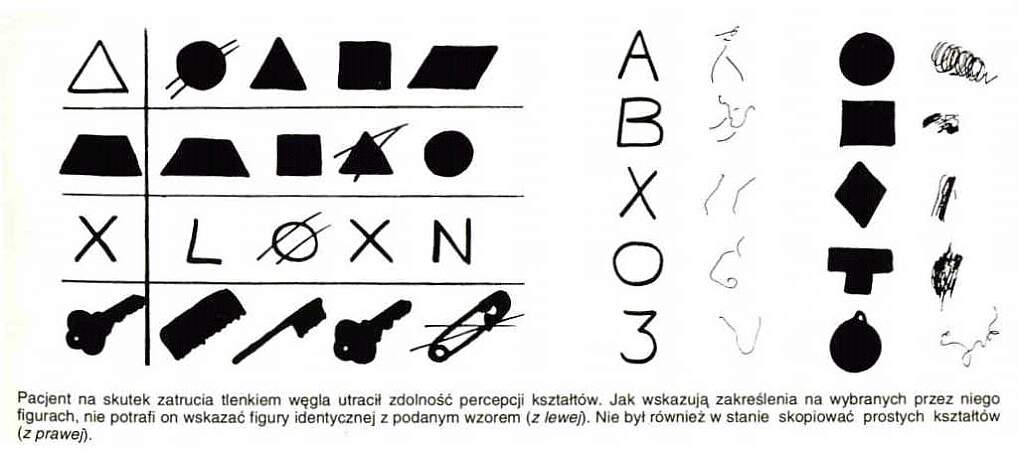

Uszkodzenia (udary, wypadki, zmiany neurodegeneracyjne) obszaru V2 wywołują zaburzoną percepcję kształtów.

Agnozja kształtu ma wiele form, nawet proste kształty mogą być niewłaściwie rozpoznawane.

Widać to w testach selekcji lub kopiowania widzianej figury, lub pisania liter czy znaków .

Pomimo prawidłowego wykonania kopii rysunków pacjent nie ma pojęcia, co przedstawiają narysowane przedmioty.